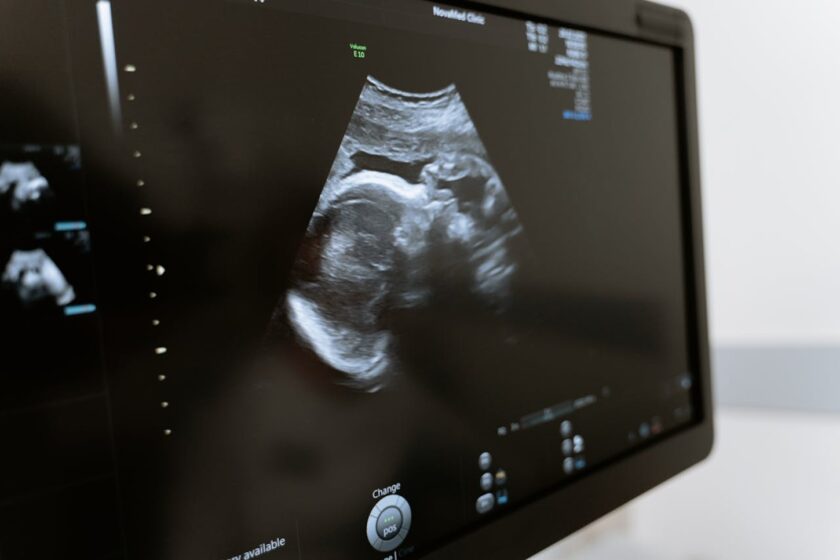

Kvalitní pracoviště proto řeší situaci páru jako celek. Nezaměřuje se jen na samotný zákrok, ale na příčinu. To může zahrnovat hormonální vyšetření, ultrazvukovou diagnostiku, spermiogram i doporučení úpravy životního stylu.